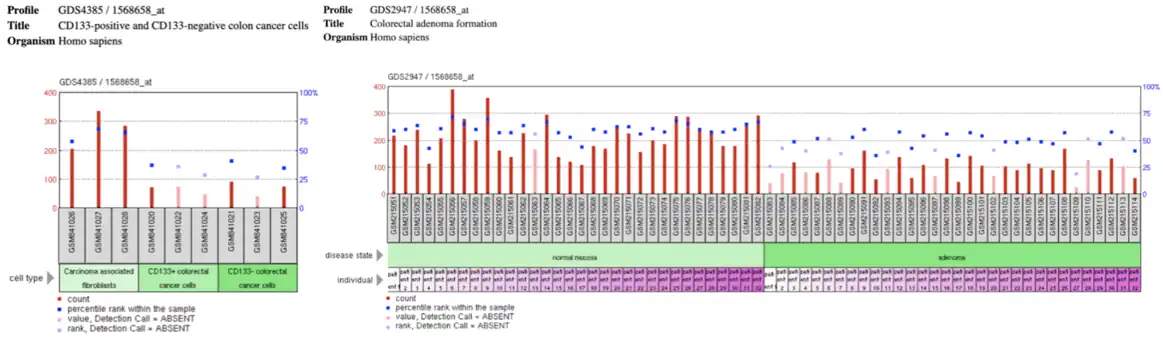

C2orf74 is expressed at minimal levels in several cell types. Due to the low levels of expression, meaningful trends in localization are difficult to discern.[2] In situ hybridization of C2orf74 and some RNA sequencing assays indicate potential for localization in the cerebellum.[2][21] Microarray data from NCBI GEO indicates lower levels of C2orf74 expression in individuals with colorectal tumors such as adenomas or cancerous colorectal tumors when compared to normal mucosa or tumors of non-colorectal origin such as carcinomas.[22]

Several studies have been able to link differential C2orf74 functionality to bowel disease. Two separate studies have identified C2orf74 as a potential susceptibility locus for Crohn's disease.[6][7] Furthermore, various studies reported in NCBI GEO show differential expression of C2orf74 in benign and cancerous colorectal tumor tissues.[29]